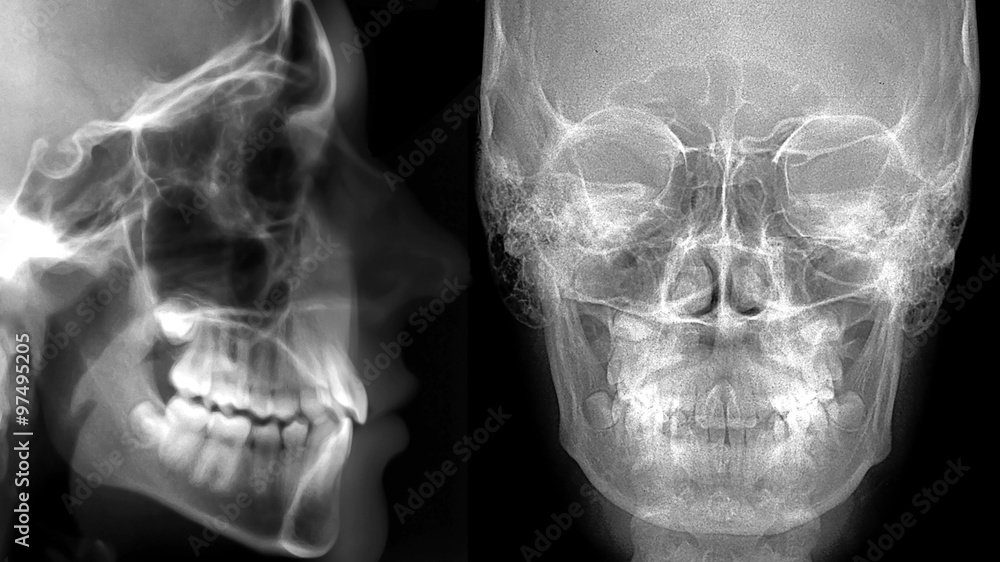

PANTOMOGRAM I CEFALOMETRIA

Zdjęcie cefalometryczne, to zdjęcie rentgenowskie, ukazujące rzut boczny czaszki. Zdjęcie niezbędne do diagnozy w leczeniu ortodontycznym.